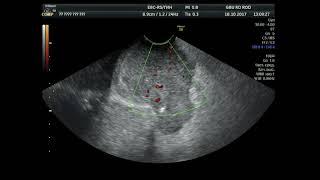

Самостоятельно определить злокачественную патологию практически невозможно. В России он ежегодно диагностируется почти у 70 тысяч женщин, болеют им и мужчины. Существует целая группа незлокачественных новообразований, которые могут привести к раку молочной железы. Обязательное выполнение трепан-биопсии с гистологическим и иммуногистохимическим исследованием.